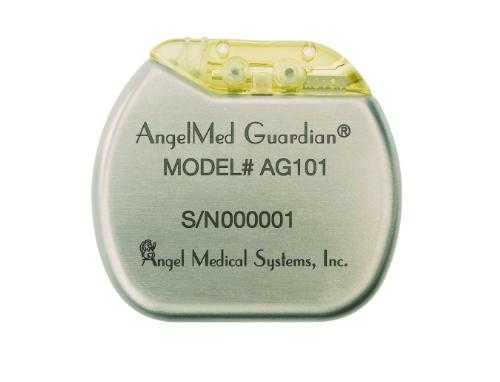

La delibera è frutto del lavoro condiviso di associazioni, comitati e coordinamenti espressione di tutti i Municipi di Roma per chiedere che anche nella capitale dItalia si faccia la raccolta differenziata: per proteggere il paesaggio, tutelare lambiente, salvaguardare la salute dei nostri figli e anche delle nostre tasche. Per ciò che riguarda le patologie cardiovascolari, in tutto il mondo la ricerca va avanti spesso - fortunatamente - facendopassi da gigante. Per alcune patologie, come quelle cardiologiche, la prevenzione appare essere l'unica via percorribile per limitare il tasso di mortalità dei pazienti,

Per ciò che riguarda le patologie cardiovascolari, in tutto il mondo la ricerca va avanti spesso - fortunatamente - facendopassi da gigante. Per alcune patologie, come quelle cardiologiche, la prevenzione appare essere l'unica via percorribile per limitare il tasso di mortalità dei pazienti, Il breve filmato racconta che la Luna si è formata quando un corpo celeste delle dimensioni di Marte ha colpito la Terra 4,5 miliardi di anni fa, causando una nube enorme che ha eruttato nello spazio. La Luna si è così staccata dalla Terra e ha iniziato a vivere di vita propria.